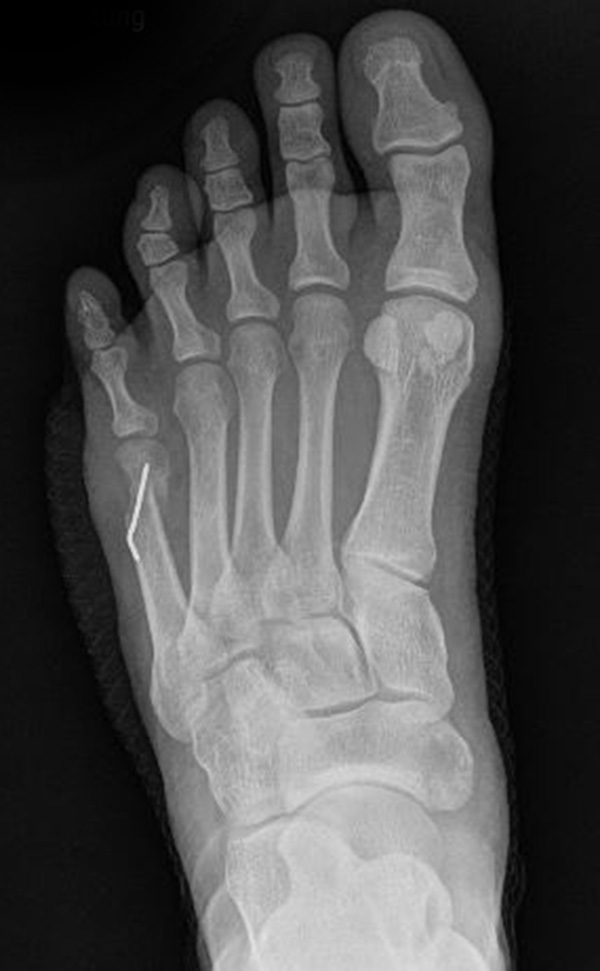

Abb. 7 a, b: Typ II Deformität mit prä- (a) und postoperativem Röntgenbild (b) mit K-Draht Osteosynthese und gleichzeitiger Hallux valgus Korrektur.